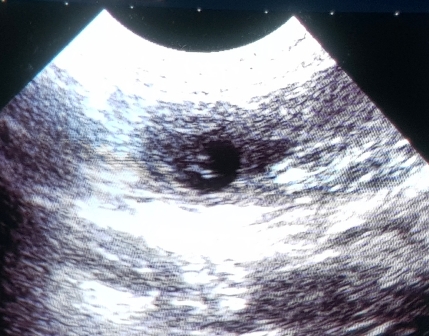

Ich weiß genau wie groß unsere Kindlys heute sind :)

Da ich das Ultraschallgerät bis zur Geburt mal wieder von unserem Wohnzimmertisch ;)

entfernen wollte(..es ist mega schwer!!), dachte ich... so gaaanz kurz kann ich doch noch mal reingucken :)

Phoebe legt sich schon alleine in unser großes Kuschelhundebett und streckt mir den Bauch entgegen ;)

.. sie sind 3 cm lang und ca. 1,4 cm breit, das passt genau in die Zeit, glaube ich!

Ich lese mich so nach und nach durch das riesige Buch, welches dem Gerät beilag.

Und langsam kann ich die Feinheiten etwas besser nutzen :)

Sechs Kindlys konnte ich heute entdecken, alle mit schlagenden Herzchen, der Rest war undurchdringlich.

Phoebe hat ein sehr dichtes Fell und hatte gut gegessen. Also weiter alles offen!!